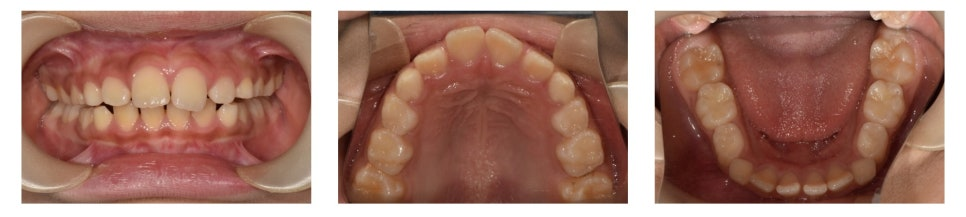

초진 구내 사진을 보면,

▶ 위·아래 앞니가 살짝 삐뚤빼뚤한 상태(crowding)

▶ 상악 전치부가 많이 튀어나와 있는 모습(large overjet)

▶ 깊게 물려서 상악 전치부가 하악 전치부를 많이 덮고 있는 상태(deep bite)

를 확인할 수 있었습니다.